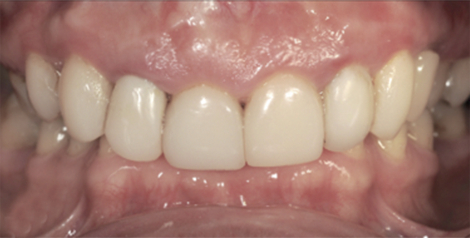

ПОСЛЕ

Проведено лечение брекет-системой, установлены имплантаты в жевательном отделе, изготовлены виниры и безметалловые коронки на зубы в зоне улыбки, восстановлена дикция, устранены морщины в уголках рта.